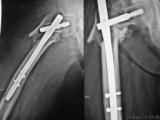

Re: неправильно-срастающийся черезвертельный перелом после Gamma-long

Ув. коллега, повторите снимки с лучшим качеством, если есть первичные тоже.

Учитывая такой угол в конструкции надо думать о ее разрушении.

Возможно, получится даже пересинтезировать этим же

гвоздем.

Надо бы посмотреть на снимки в большем разрешении.

Вальгизирующая остеотомия, фиксация клинковой 130 градусной в один или два изгиба в зависимости от СORA по Paley. Пример- пациент тоже из Киева, у нас в Киеве, к сожалению, эпидемия постравматических варусных деформаций.

BTW эта Gamma не такая уж long...

BTW эта Гамма вообще не "Гамма", а контрафакт. Опасайтесь дешевых подделок!

Уважаемые коллеги!

Судя по нынешнему х-ray изначально допущена техническая ошибка. Если есть возможность можно показать первичные снимки, я боле склонен к тому что это результат ятрогении т.е. зона ската разрушена при введении штифта. На мой взгляд: удаление металлоконструкции, открытая репозиция восстановление ШДУ с остеотомией (может быть необходима костная пластика) и остеосинтез PFN. То, что эпидемия по Киеву, конечно треубет пересмотра в обществе травматологов, чтобы найти причину проблемы. Удачи.